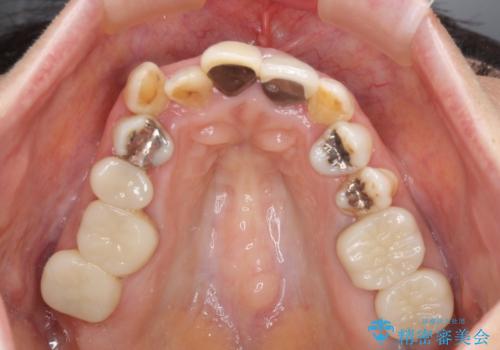

奥歯の銀歯は、セラミッククラウンを装着するには歯の高さが不十分であり、そのままでは矯正治療を行うことが困難であるため、歯冠長延長術を行うこととしました。

また、根管治療の必要な歯がいくつかあるため、歯周外科治療の治癒期間を利用して根管治療を行い、その後インビザラインにて矯正治療を行うこととしました。

外科処置に対する恐怖心が強かったため、処置の際には静脈内鎮静法を用いて、リラックスした状態で行いました。